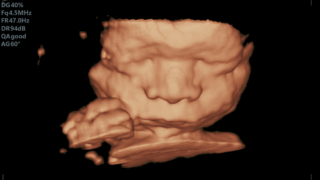

1ヶ月の休暇はあっという間ですすくすくと我が子は育ってきました臍の緒も取れて目も以前よりぱっちり開くことが増えましたまだまだお腹すいたとうんちでしか泣きません来月にはもう少し意思表示してくれるかなと大変だろうけど楽しみにしています